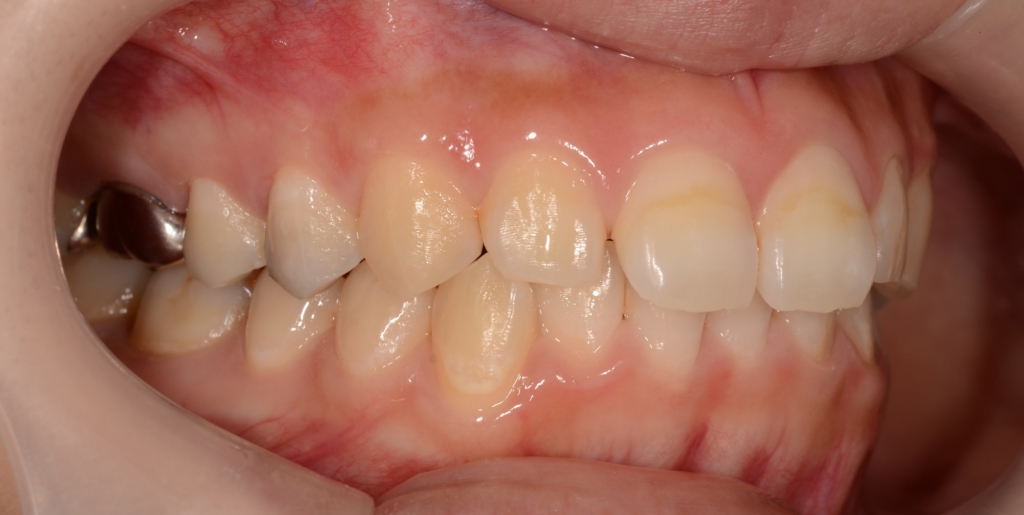

【Before】

治療に伴う歯肉の変化をお見せしましょう。

上段が圧下治療開始時点、下段が圧下治療終了後 になります。